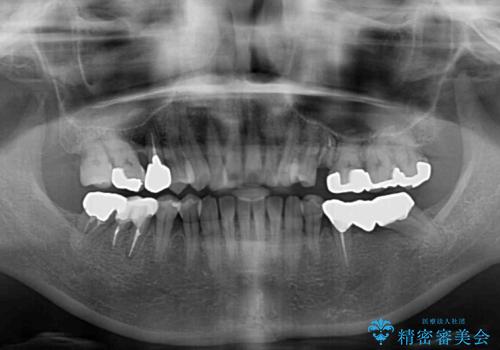

- 飛び出した上顎前歯と正中のズレを気にして来院された患者様です。

上顎正中が右側にずれていたので、むし歯が酷く抜歯が必要な左側臼歯を抜歯して正中を改善することとしました。

左下には新しいセラミックのブリッジが装着されていたため、ブリッジを壊さずに改善できるところまで咬み合わせを改善していくこととしました。

右上小臼歯は銀歯が装着されており、ワイヤー矯正の装置が装着できないため、事前に仮歯に変えてから矯正治療を行い、その後オールセラミッククラウンにて補綴治療を行いました。